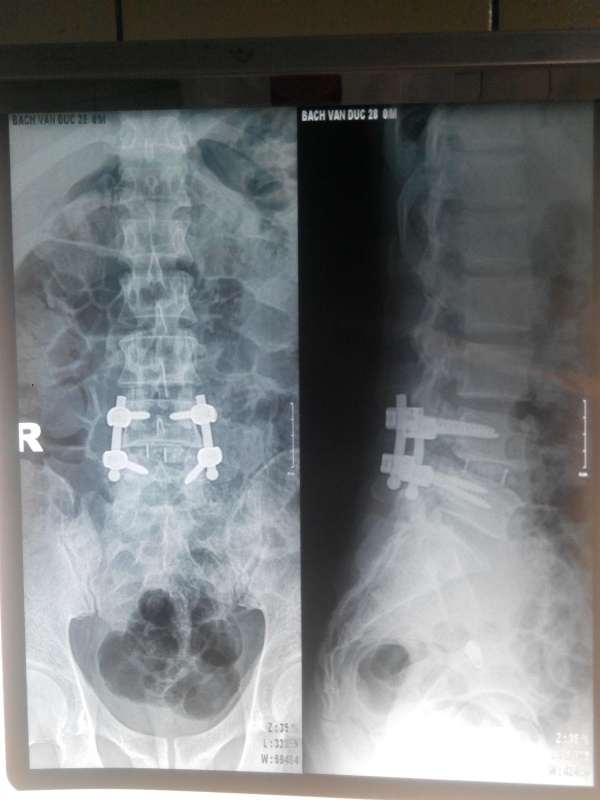

Sau mổ, 100% các trường hợp có đau vết mổ, 5 BN (16,7%) còn rối loạn vận động. 100% bệnh nhân hết trượt đốt sống. Khoảng cách gian đốt được cải thiện, trung bình 12,87 ± 0,68 mm (p < 0,05). Độ chính xác của vít theo tiêu chuẩn của Lonstein đạt 97,5%. 100% BN có vị trí miếng ghép nhân tạo nằm ở 2/3 trước thân đốt sống trượt. Thời gian nằm viện trung bình sau mổ là 6,4 ± 0,7 ngày. Sau khám lại, VAS lưng trung bình 1,3 ± 0,5 điểm, VAS rễ trung bình 0,3 ± 0,4 điểm. 3 bệnh nhân còn yếu cổ bàn chân do tổn thương trước mổ. ODI trung bình 18,9 ± 11,01 % (10 – 60%). Chiều cao gian đốt không thay đổi so với sau mổ, trung bình 12,87 ± 0,68 mm. 100% BN liền xương tốt, không có trường hợp nào khớp giả. Đánh giá theo MacNab có 86,7% kết quả tốt, 13,3% có kết quả khá.

Chẩn đoán hình ảnh sau mổ

Mức độ nắn chỉnh độ trượt: Trước mổ đa phần BN trượt độ I (86,7%). Xquang sau mổ 100% BN đã được nắn chỉnh hết trượt, sự khác biệt có ý nghĩa thống kê (p < 0,05). Việc nắn chỉnh cột sống có thể làm thương tổn thần kinh thứ phát. Trên thực tế việc nắn chỉnh biến dạng cột sống không đơn giản, phụ thuộc vào kỹ thuật, kinh nghiệm của từng phẫu thuật viên. Nắn chỉnh hoàn toàn di lệch đốt sống làm tăng diện ghép xương đem lại kết quả tốt, điều này thực hiện dễ ở BN có trượt độ I, II như trong nghiên cứu của chúng tôi. Những BN có độ trượt nặng nhiều tác giả quan điểm không cố gắng nắn chỉnh hết di lệch trượt để hạn chế các thương tổn thứ phát.

Cải thiện chiều cao gian thân đốt sống trượt: Chiều cao gian thân đốt sống trượt chính là chiều cao khối xương ghép. Trên Xquang sau mổ độ cản quang của ổ xương ghép đậm, không có sự di chuyển của miếng ghép nhân tạo và xương vào trong ống sống. Trước mổ chiều cao gian đốt sống trượt 8,0 ± 2,5 mm, sau mổ được cải thiện rõ, trung bình 12,87 ± 0,68 mm (p<0,05). Nghiên cứu của McAfee và cộng sự cũng có sự cải thiện chiều cao gian đốt sau mổ từ trung bình 5,6mm đến 9,3mm, đánh giá kết quả xa sau 3 tháng cho tỷ lệ liền xương tới 98% [15].

Độ chính xác vít, miếng ghép nhân tạo: Độ chính xác của kỹ thuật bắt vít sẽ giúp giảm thiểu tối đa các tổn thương và biến chứng, đảm bảo được lực cần thiết trong việc nắn chỉnh giải phẫu trong mổ, tạo điều kiện thuận lợi cho quá trình liền xương sau mổ. Gertzbein S.D. và cộng sự qua phẫu thuật bắt vít qua cuống sử dụng hệ thống AO thấy 6% vít bắt vào trong ống tuỷ 4-8mm. Lonstein thông báo trong năm đầu kinh nghiệm trong phẫu thuật bắt vít cuống cung thấy 18,3% (trong tổng số 327 vít) bắt sai vị trí [17]. Chúng tôi phẫu thuật 30 BN với 120 vít đã được bắt để cố định đốt sống trượt. Đánh giá độ chính xác của vít dựa trên chẩn đoán hình ảnh theo tiêu chuẩn của Lonstein chúng tôi thấy tỷ lệ vít bắt đúng tiêu chuẩn đạt 97,5%, 1 vít bắt vào bờ trên cuống và sát bờ trên thân đốt, 1 vít bắt vào cuống nhưng ra ngoài thân đốt, Vít vượt quá 2 bờ thân đốt trên phim nghiêng. Tuy nhiên khám lại sau mổ những trường hợp này chúng tôi thấy không có dấu hiệu thần kinh xấu đi hay dấu hiệu đau hoặc tổn thương của rễ tương ứng. Điều này có thể cho rằng việc kiểm tra C-arm trong mổ chưa đầy đủ dẫn tới chưa kiểm soát được tình trạng bắt vít. Theo Jurgen Harms, cột trụ sau sẽ chịu khoảng 20% còn cột trước sẽ chịu 80% trọng lực. Do đó vị trí miếng ghép nhân tạo đóng vai trò quan trọng trong việc trả lại giải phẫu góc ưỡn vùng cột sống thắt lưng, nâng cao khoảng gian đĩa, tăng thể tích khối xương ghép và hạn chế các biểu hiện lâm sàng do chèn ép rễ, ngách bên. Nghiên cứu của chúng tôi 100% số lượng miếng ghép nhân tạo ở 2/3 trước thân đốt sống trượt ở mức tốt.

Chẩn đoán hình ảnh sau phẫu thuật

Chiều cao gian đốt sống trượt: Chiều cao gian đốt được khôi phục sau phẫu thuật trung bình 12,87 ± 0,68 mm, khác biệt có ý nghĩa thống kê so với trước phẫu thuật (p<0,05). So với thời điểm sau mổ không có sự khác biệt, cho thấy sự chắc chắn của khối xương ghép. Nghiên cứu của Herkowitz trên 50 BN được ghép xương liên thân đốt không sử dụng miếng ghép nhân tạo chiều cao đĩa đệm trước mổ 6,8mm theo dõi xa sau mổ chiều cao gian đốt chỉ còn 5,7mm, tỷ lệ liền xương sau mổ là 77%, dẫn tới kết quả tốt sau mổ 44%, khá 52% và trung bình là 4% [22].

Độ liền xương: 100% BN được sử dụng dụng vật liệu ghép xương là miếng ghép nhân tạo và xương cung sau tự thân cắt nhỏ. Ngoài những ưu điểm có độ cứng thích hợp, đạt tỷ lệ liền xương cao, ghép xương cung sau cắt nhỏ còn nhiều ưu điểm như: tiện lợi không phải thêm vết phẫu thuật, không có biến chứng tại chỗ lấy xương, rút ngắn thời gian phẫu thuật, giảm lượng máu mất, giảm chi phí. Trên thực tế lựa chọn phương pháp phẫu thuật và vật liệu ghép phụ thuộc vào kinh nghiệm của phẫu thuật viên, mức độ nặng của bệnh nhân, trang bị của cơ sở y tế. Tuy nhiên ghép xương liên thân đốt lối vào phía sau có tỷ lệ liền xương và kết quả điều trị tốt nhất. Ghép xương liên thân đốt lối vào phía sau cũng có những nhược điểm như sẹo dính quanh màng cứng, tổn thương rễ do vén quá mức. Hiện nay, xu hướng áp dụng kỹ thuật GXLTĐ qua lỗ liên hợp (TLIF) có thể hạn chế những nhược điểm trên. Những BN đã phẫu thuật nhiều lần, sẹo dính quanh màng cứng là một khó khăn cho việc lựa chọn GXLTĐ từ phía sau (PLIF). Tuy nhiên ở những BN có độ trượt lớn như độ III, IV thì vấn đề kết hợp TLIF và PLIF lại có ưu thế thuận lợi cho việc giải ép và nắn chỉnh độ trượt. Do vậy hiện nay hầu hết các trung tâm phẫu thuật ở nước ta chủ yếu vẫn đang áp dụng kết hợp cả hai kỹ thuật này.

Theo tiêu chuẩn của Bridwell, tỷ lệ liền xương theo dõi xa sau mổ có 96,7% BN xương ghép tốt, 3,3% liền xương trung bình tương ứng với 1 BN tăng thấu quang tại vị trí miếng ghép [13]. Tuy nhiên BN không bị gãy vít và không có triệu chứng lâm sàng, có thể đeo áo hỗ trợ và theo dõi thêm sau đánh giá lại sau này. Kuang và cộng sự theo dõi sau 6,5 tháng trên 42 BN lại có tỷ lệ liền xương gần như 100% [18]. Lý giải điều này chúng tôi cho rằng trong nghiên cứu của tác giả hầu hết các BN có tuổi đời thấp, tốc độ liền xương tốt hơn.

Trước phẫu thuật đa phần BN bị trượt độ I, song Xquang quy ước sau phẫu thuật 100% BN không còn trượt. Theo dõi xa các BN đều không trượt tiến triển, không có BN gãy vít sau phẫu thuật và di lệch miếng ghép. Nghiên cứu của Nguyễn Vũ, Nguyễn Bá Hậu cũng cho kết quả tương tự [1], [5].